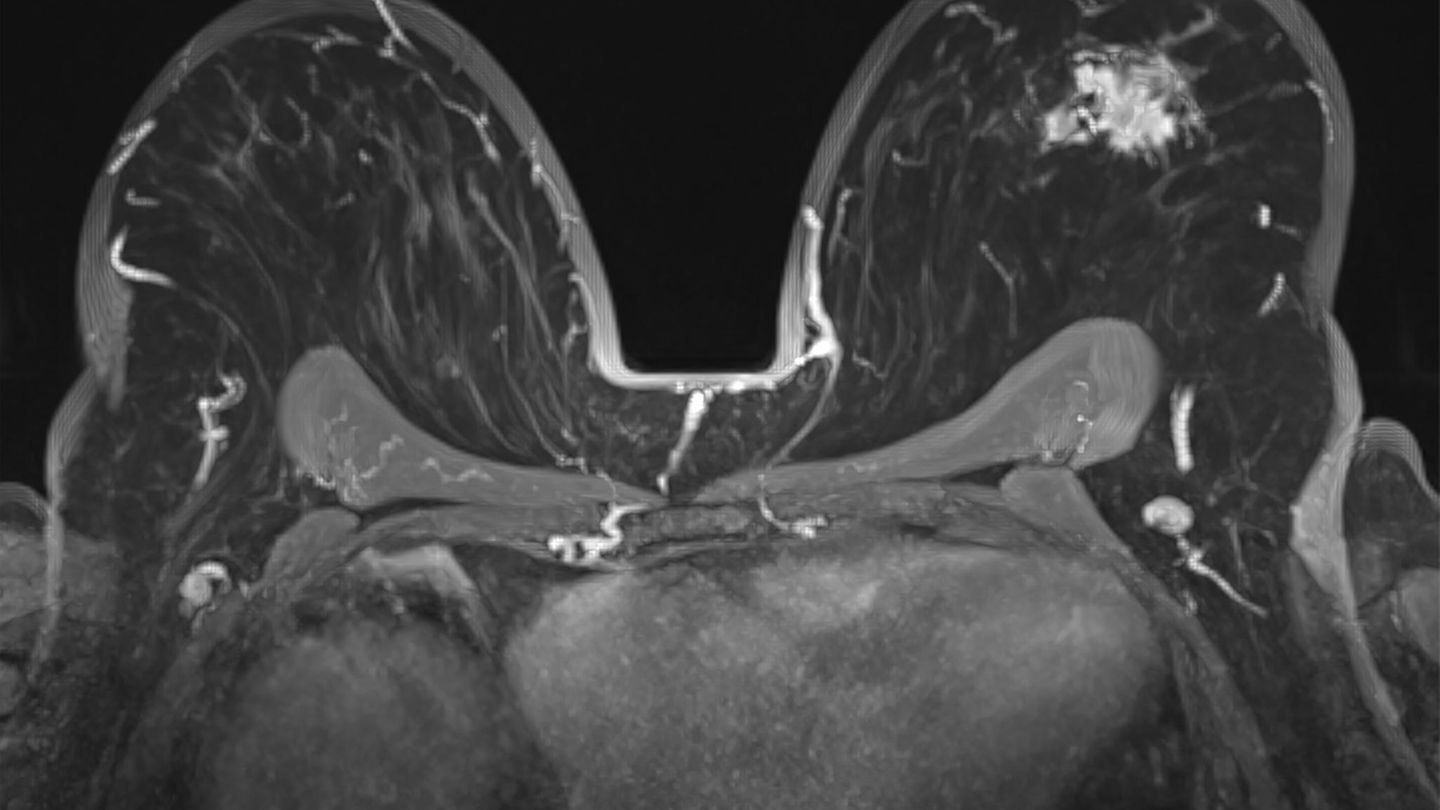

MRT Aufnahme einer Brust mit Brustkrebs

Kein klassischer Brustkrebs – der maligne Phyllodes-Tumor

Der maligne Phyllodes-Tumor entsteht im Bindegewebe der Brust und wächst oft rasch, aber schmerzlos. Rückfälle sind häufig, Metastasen möglich. Seine Seltenheit erklärt sich aus dem Zelltyp: Stromale Bindegewebszellen teilen sich deutlich seltener als Drüsenzellen und reagieren kaum auf Hormone. Damit fehlt ein zentraler Wachstumstreiber vieler Brustkrebserkrankungen – ein wirksamer biologischer Schutz vor Entartung.

© Paul Biris / Getty Images